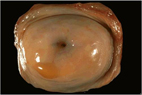

正常的子宮頸

一般只要病人沒有嚴重內科病史,早期子宮頸癌可接受手術治療,把惡性腫瘤完整的切除。對於子宮頸癌前病變至原位癌(CIN2,CIN3),在陰道鏡檢查做完切片,得到病理結果後,只要作子宮頸圓錐狀切除手術(表一及圖二),即可達到百分之99之治癒率。仍可保留子宮及部份的子宮頸,婦女生育能力不會受到影響。但如果癌細胞侵犯至基底膜以下,進入子宮頸的間質組織時,即成為子宮頸侵襲癌了。若第一期上侵犯範圍較少(深度小於3毫米,寬度小於7毫米),則施行子宮切除手術即可,但若患者還想生育,甚至只作子宮頸圓錐狀切除手術即可。但若第一期上侵犯範圍較大(深度在3~5毫米,寬度小於7毫米),則只需作較小範圍之根治性子宮切除及雙側骨盆腔淋巴結摘除手術。若想保留子宮及生育力,亦可作根治性子宮頸切除及雙側骨盆腔淋巴結摘除手術。若是第一期下(子宮頸間質侵犯深度大於5毫米,寬度大於7毫米,惡性腫瘤仍位於子宮頸)或第二期初(惡性腫瘤侵犯至陰道)之患者,則只有施行根治性子宮切除及雙側骨盆腔淋巴結摘除手術(圖三)。

子宮頸圓錐狀切除手術( 表一)

•中、重度子宮頸上皮病變、或最早期子宮頸癌(子宮頸間質侵犯深度小於3毫米,寬度小於7毫米)。患者的局部處置,可保留生育力

子宮頸圓錐狀切除手術